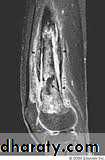

MRI is the imaging modality of choice & shows evidence of bone odema and pus accumulation in the bone & soft tissue .distinction of neoplasm from osteomyelitis :

With malignant bone tumor the radiographs are usually abnormalwhen the patient first presents , whereas with osteomyelitis the initial film are often normal .

CT & MRI more informative.